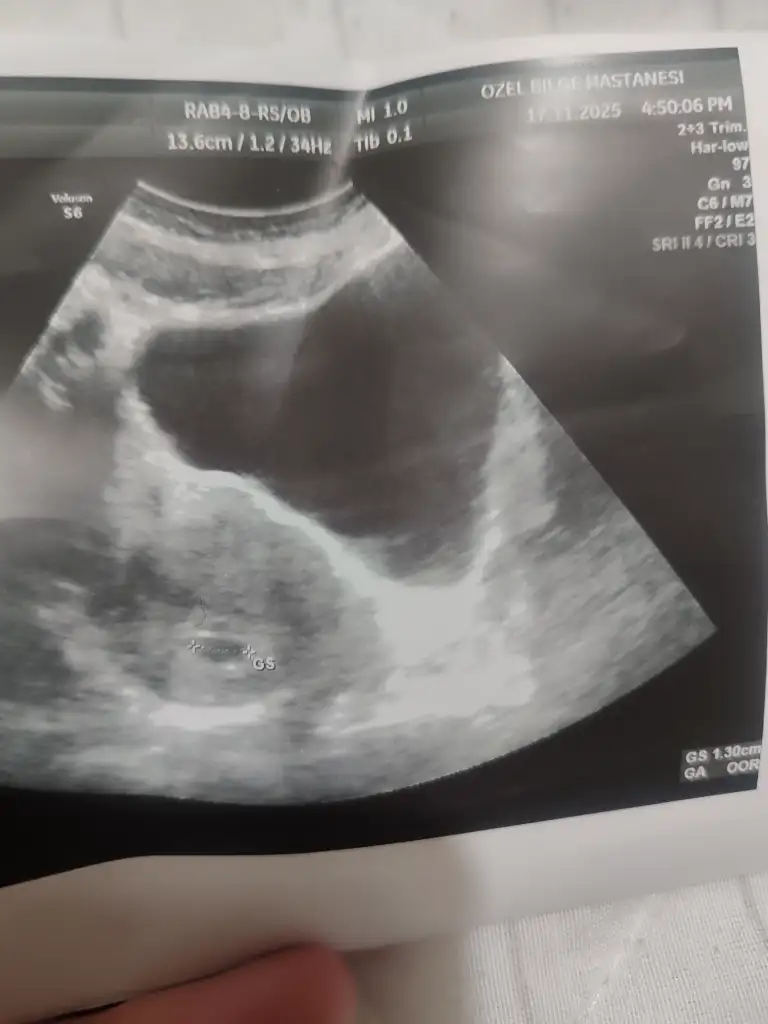

Cumartesi günü doktora gittim karından keseyi gördü 1.38 cm kese boş şuan gözükür diye düşünüyorduk haftaya pazartesi tekrar gideceğim![]()

Gözükmez canım o boyutta bende 1.30 ken kese boyum görünmemişti doktor cok normal demişti ki 1 hafta sonra hem bebişi görmüştük hem kalp atısını dinlemiştik merak etmeValla hiç keyfim yok benim 2 gündür

Kaç haftalık bu görselleerGözükmez canım o boyutta bende 1.30 ken kese boyum görünmemişti doktor cok normal demişti ki 1 hafta sonra hem bebişi görmüştük hem kalp atısını dinlemiştik merak etme

Biri 6+1 diğeri 7+1 canımKaç haftalık bu görselleer